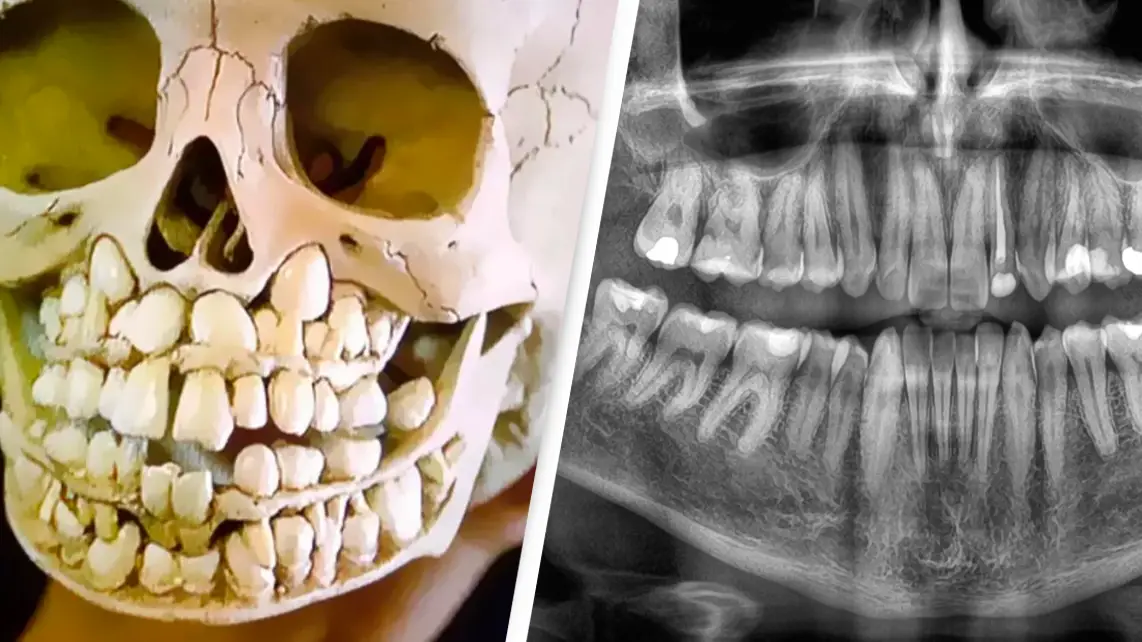

"Every child’s jaws are packed with teeth, but we don’t think about them until they start to 'erupt' in the gums," the Redditor who posted the image said.

The snap shows an unprecedented number of teeth in the gums in the child's jaw, and to be honest, it's certainly off-putting.

One person penned: "To those asking if this is real - my dentist took X-rays when I was 6 years old and showed me the images, which showed exactly this, all my adult teeth waiting underneath. As a 6-year-old I found it fascinating.

Meanwhile, a third quipped: "Sure, it looks creepy with its double row of teeth, but if you think about it, it's really just a perfectly normal skull of a dead child," and a fourth remarked: "Yup, one of the many horrors found in human body."

While it's not been confirmed how old the child whose skull this is, many in the comments section speculated the child was likely around the 6-8 age range.